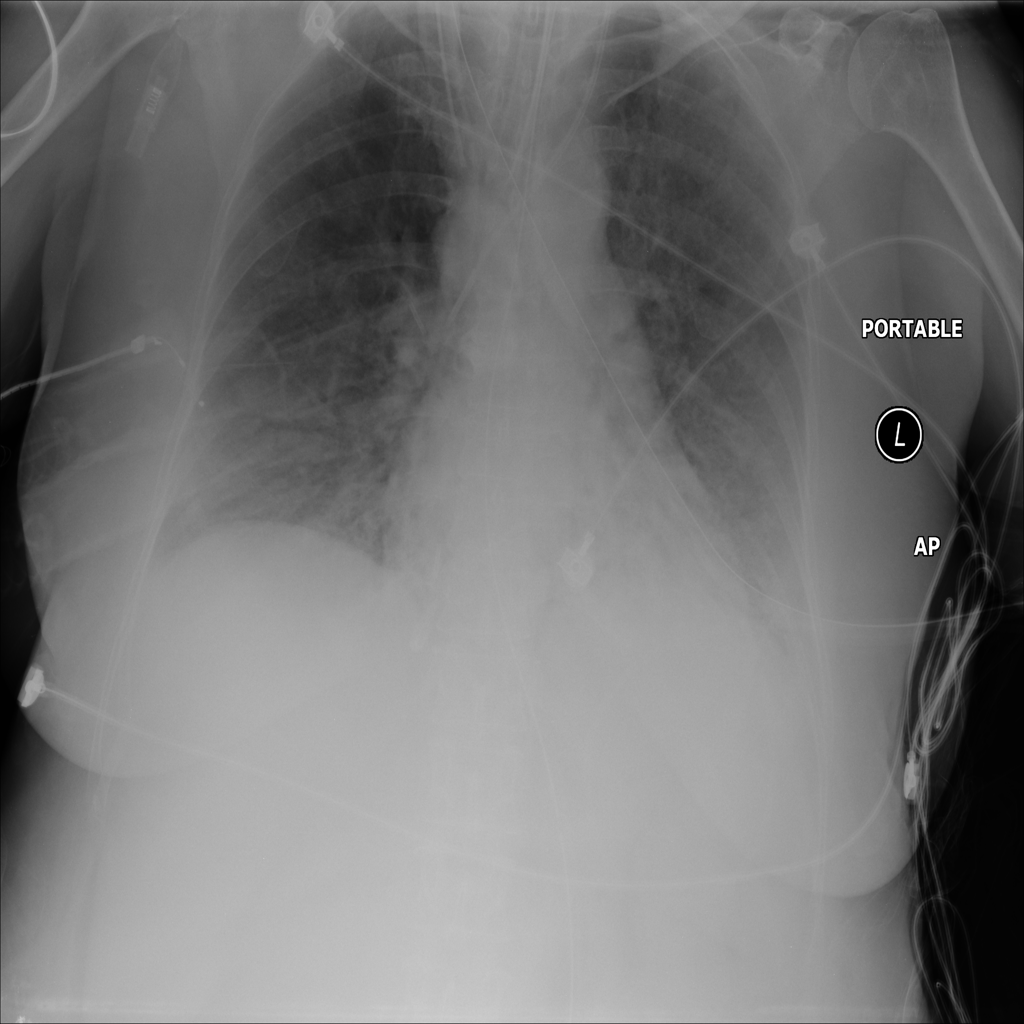

PAT-C1A7 · IMG-055Consolidation

PAT-C1A7 · IMG-055

AP